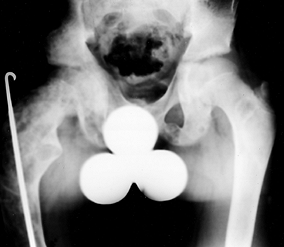

present. Bowing of the long bones and genu valgum are common.

can be seen at the terminal tufts of the distal phalanges, the

symphysis pubis (Fig. 180.28), and the end of

the clavicle. Metaphyseal resorption of bone leads to widened physes

and slipped capital femoral epiphysis (SCFE; see Chapter 172) (Fig. 180.29). Disturbance of the proximal lateral tibial physis with associated genu valgum has been described (161).

![]() |

|

Figure 180.28. Resorption of the pubis due to renal osteodystrophy.

Figure 180.29.

Physeal widening and slipped capital femoral epiphysis in a 7-year-old boy presenting with hip pain. A diagnosis of renal failure was made. |